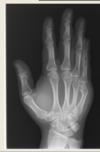

What pathological disease does this X-Ray show?

Osteoarthritis (most noticeable in Distal interphalangeal joints 2,3,4 in the DP view (left image))